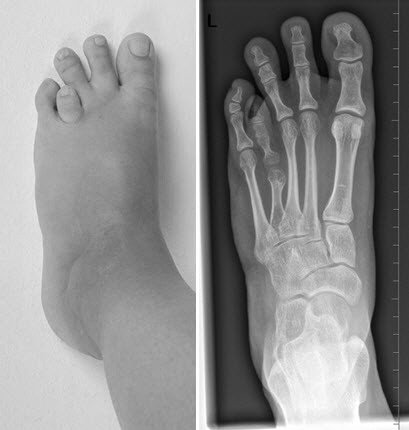

Zehenverlängerung bei Brachydaktylie

Vor der Operation

Es besteht eine angeborene Verkürzung der 4. Zehe. Die Patientin hat Schmerzen vor allem im Bereich der Fusssohle und teilweise auch Probleme mit den Schuhen. Zudem stört Sie sich sehr am Aussehen und zieht keine offenen Schuhe an.